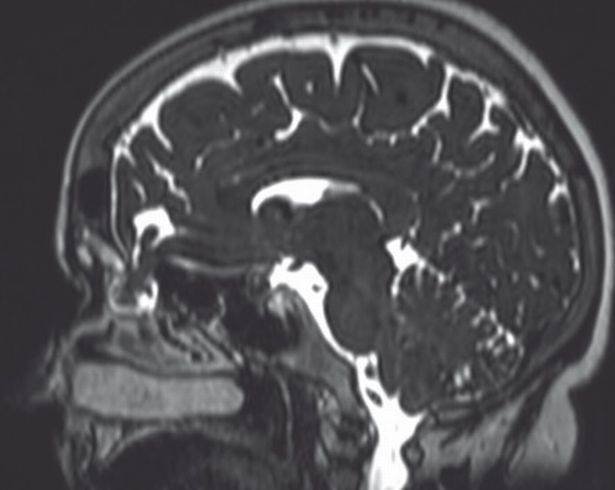

A vítima do erro no teste foi encaminhada aos hospitais da Universidade de Iowa, onde descobriram, por meio de tomografia e ressonância magnética, uma massa no meio da cavidade nasal direita.

Ressonância de paciente

Uma equipe de especialistas liderados pelo Dr. Christopher Blake Sullivan, drenou a massa e constatou vazamento de líquido cefalorraquidiano (LCR), que se encontra no cérebro e na coluna.